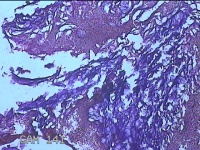

右侧颜面部结节

性别

男

年龄

35岁

临床诊断

皮脂腺囊肿

一般病史

发现右侧颜面部结节9个月余,无明显疼痛及不适。

标本名称

大体所见

灰白暗红色带皮肤样结节3x2x0.8cm一堆,表面糜烂。